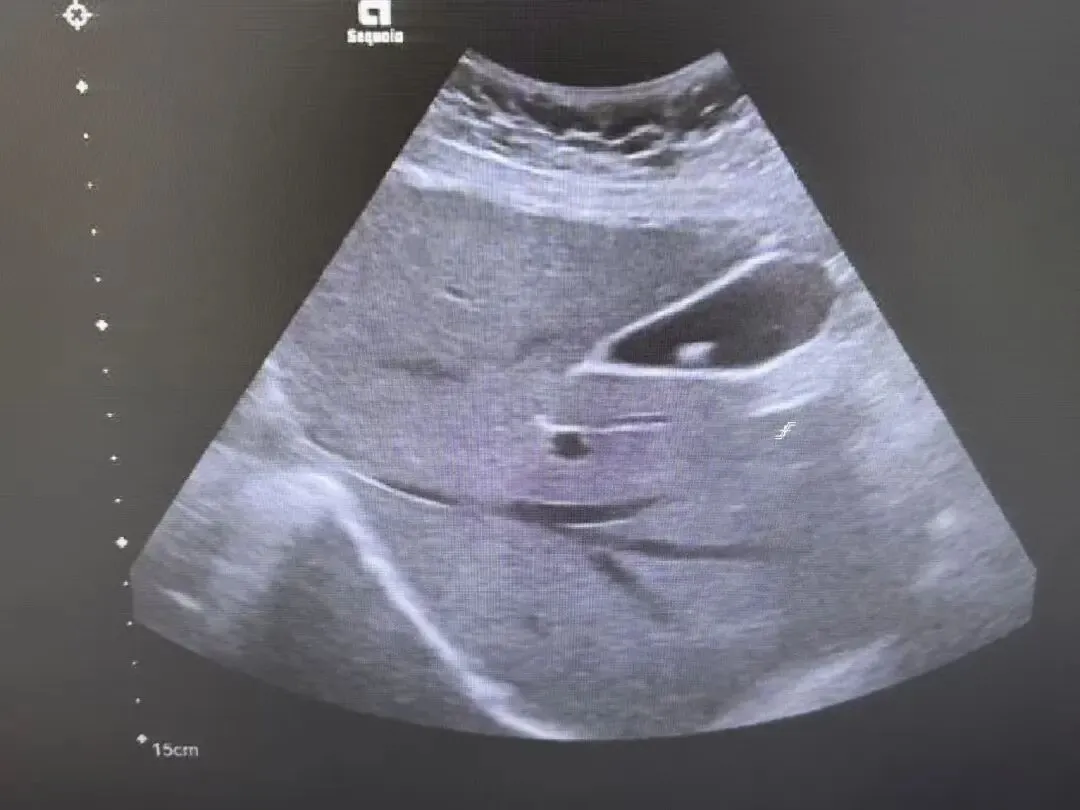

胆囊颈部结石

胆囊颈部强回声,后方伴声影,胆囊内充满稀疏的细小光点。